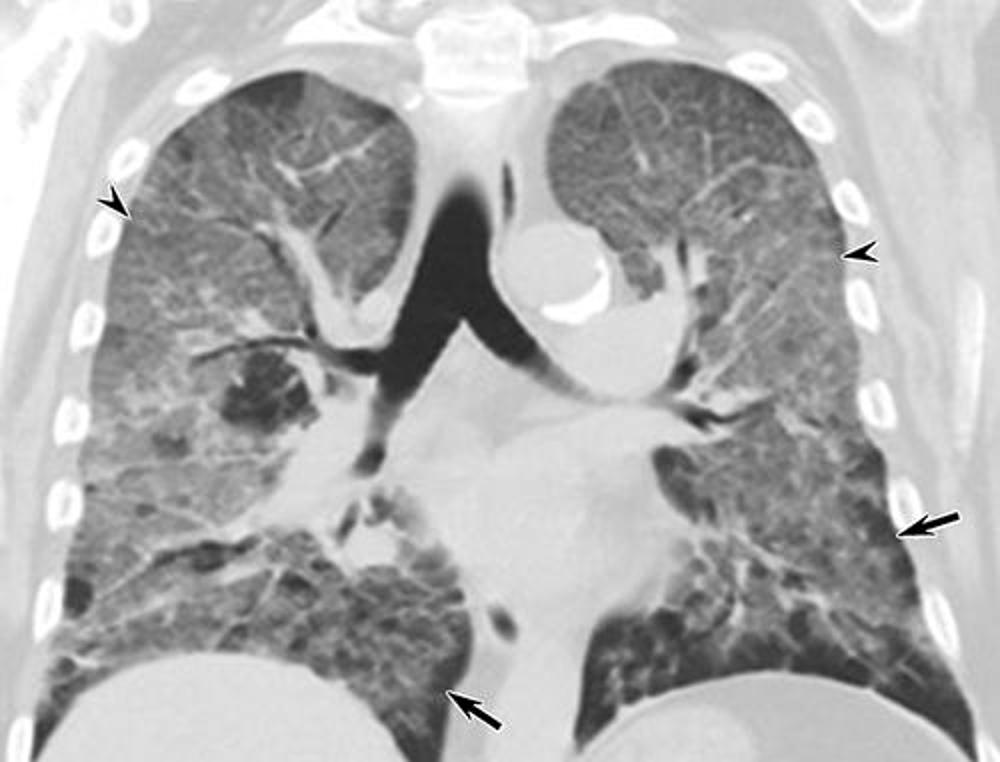

Figure 3. Electronic cigarette or vaping product use–associated lung injury in a 67-year-old man manifesting as a crazy paving–like pattern at CT. Coronal unenhanced CT image at presentation shows multifocal, bilateral ground-glass opacity associated with smooth interlobular septal thickening (arrowheads) and intralobular interstitial thickening. Areas of subpleural sparing (arrows) are present.